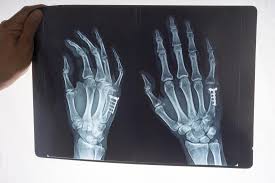

Grade 2 Ligament Tear Wrist : Why Does The Pinky Side Of My Wrist Hurt Ulnar Fovea Pain Braithwaite Physiotherapy At Avenue And Bloor In Toronto / The scapholunate ligament is a key element in stabilizing the foundation of the wrist (the scapholunate joint).

Wrist ligament tears may be classified as: Complete tear of the ligament. Grade 2 consists of a partial tear, while a complete tear is a grade 3. Athletes are particularly prone to wrist sprain. Acute trauma or repetitive use over time can lead to tears in the cartilage and/or ligaments.

Occurrence of torn ligament in wrist involves the cobweb of many bones held together with the help of ligaments. Grade 2 sprains — the ligament is stretched, and it could be partially torn. This is a severe injury and usually requires medical or surgical care. More severe damage with partial tearing of the wrist ligaments is called a moderate (grade ii) wrist sprain. Grade 3 sprains — complete ligament tear. Acute trauma or repetitive use over time can lead to tears in the cartilage and/or ligaments. Types of wrist ligament tears. A grade 2 (moderate) sprain may result in a partial ligament tear.

The repair process of ligament tear is different from other soft tissues. The ligaments are stretched, but not torn. A torn ligament causes the wrist bones to move out of their position, which in turn leads to wrist instability as the sprained (torn) ligament can no longer support the wrist bones. As a result, the joint may show abnormal looseness. The ligaments are partially torn. Ligament injuries are graded from one to three based upon their severity. This indicates that the ligament has a. Ligaments are susceptible to injury which is called a sprain. The scapholunate ligament is a key element in stabilizing the foundation of the wrist (the scapholunate joint). Intermediate sprain with partial thickness tear of the ligament A grade 1 (mild) sprain usually involves stretching of a ligament. Types of wrist ligament tears. Is a partial sprain without instability.